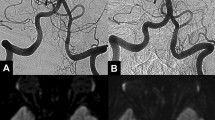

A patient rendered acutely quadriplegic in an automobile accident was shown by angiography to have occlusion of the left vertebral artery. One month later, he abruptly became unconscious, apneic and died. Autopsy showed an organised thrombus in the left vertebral artery and a fresh thrombus occluding the entire basilar artery. This case differs from previously reported cases of traumatic vertebral artery thrombosis wherein symptoms of brain stem infarction were more immediately evident.